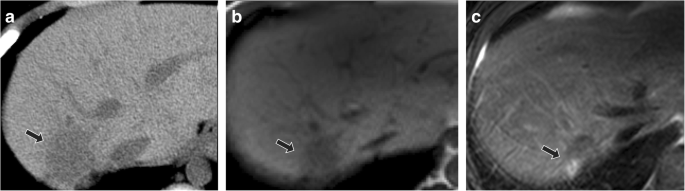

In one large ultrasound study of Gaucher disease patients, focal liver lesions were identified in just under 5% of individuals; the majority of which were multiple hyperechoic lesions [39]. Authors have suggested that such small, hyperechoic lesions do not merit biopsy if slowly growing, as they are thought to reflect focal accumulation of Gaucher cells [39]. On the other hand, early studies of MRI in Gaucher disease identified focal signal abnormalities in about one-fifth of patients [51]. Such focal accumulations of Gaucher cells are thought to be hypoattenuating on CT, hypointense on T1-weighted imaging, and heterogeneous on T2-weighted imaging (Fig. 3).

Focal Gaucher cell accumulation in the liver. Axial non-contrast abdominal CT (a) demonstrates a focal hypoattenuating hepatic lesion (arrow) in the posterior right hepatic lobe in 10-year-old male with type 1 Gaucher disease. At follow-up at 16 years of age with unenhanced MRI, lesion (arrow) was unchanged in size with T1-weighted hypointense (b) and mixed T2-weighted signal intensity (c). Findings are most consistent with focal Gaucher cell deposition (“Gaucheroma”)